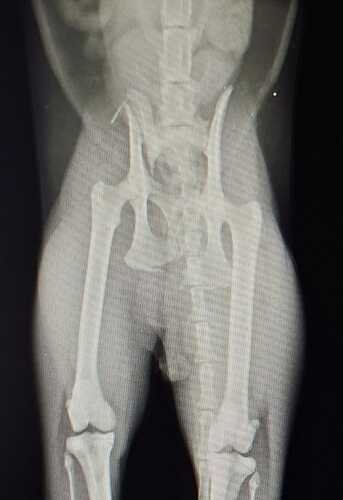

No dia 20/11/25, aconteceu o imprevisto: o Akira foi atropelado e levado imediatamente a uma clínica 24h. No dia 21/11/25, o raio-x revelou uma fratura na pelve (asa de íleo direito e terço médio do ísquio), e agora ele precisa de cirurgia ortopédica para se recuperar e voltar a ser o gatinho ativo que conhecemos.